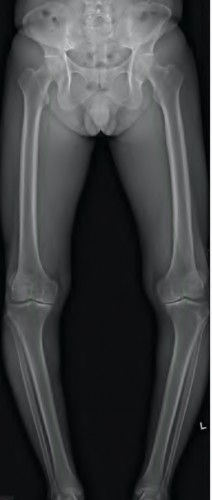

Figures A and B are pre-operative and intra-operative radiographs of a 67-year-old male that has undergone a left total hip arthroplasty under general anesthesia. The patient had no motor deficits preoperatively. During the operation, the trial acetabular and femoral components were positioned and reduced with no complication. Intraoperative leg lengths were equal. Before implanting the real components, the surgeon and anaesthesiologist performed a wake up test, which revealed that the patient was unable to dorsiflex the left foot. What would be the most appropriate next step in the management of this patient?

This patient has undergone a left THA with significant leg lengthening. The biggest concern is stretch to the sciatic nerve. The most appropriate step at this stage would be to perform a subtrochanteric osteotomy to decrease leg length and sciatic nerve stretch.

Patients with DDH that have undergone a large limb-lengthening procedure are at a greater risk due to the significant stretch of the sciatic nerve. Intraoperative procedures that have been shown to prevent this outcome include good pre-operative planning, limb lengthening